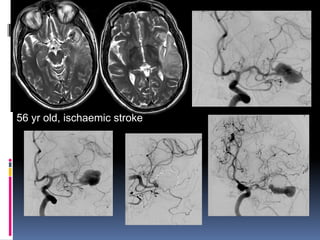

56 yr old, ischaemic stroke

56 yr old,ischaemic stroke